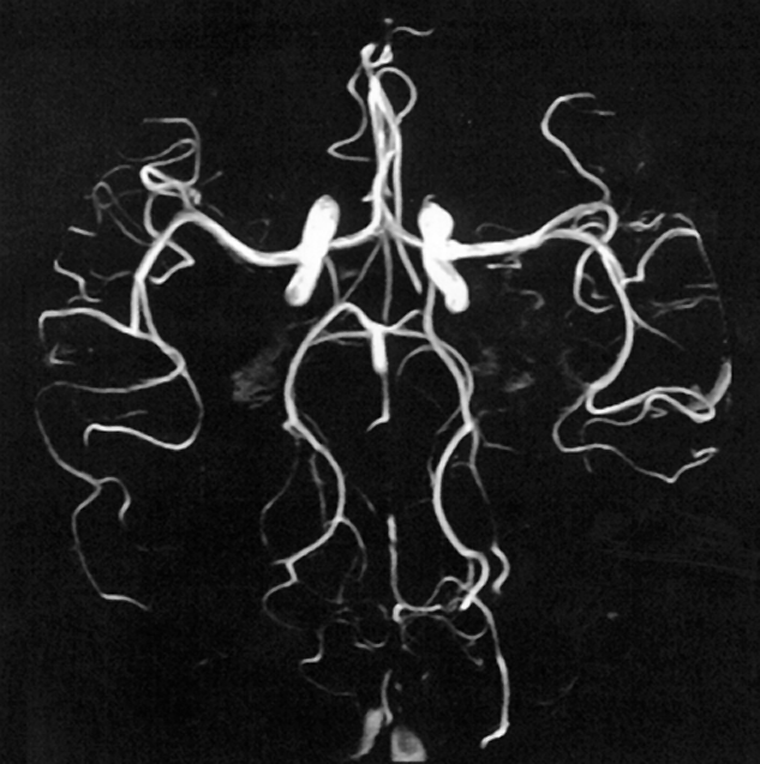

Figura 14-13:

Phase-contrast angiography.